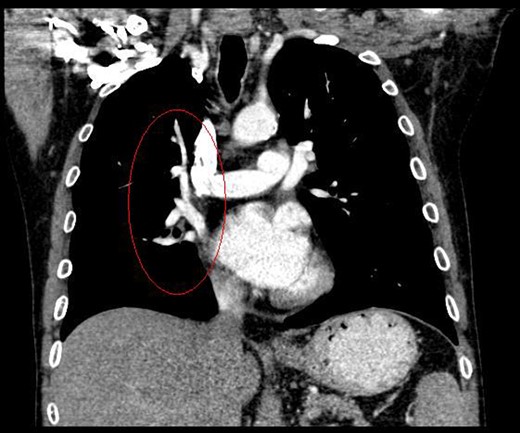

During discussions at the multidisciplinary team meeting, the computed tomography scans of his thorax were reviewed by our radiology colleagues and an anomalous right upper lobe vein was identified.

The patient underwent a right postero-lateral thoracotomy. The right upper lobe pulmonary artery and vein were identified and divided with vascular Endo GIA™ staples. Lymphadenectomy was performed in the draining lymph nodes and we proceeded to isolate the upper lobe bronchus. Prior knowledge of an anomalous venous drainage of the upper lobe made us adopt a cautious approach during dissection posterior to the right upper lobe bronchus and a vascular structure was identified that could be traced in the left atrium; thus, it was found to be an anomalous upper lobe pulmonary vein. The anomalous vein was divided with vascular Endo GIA™ staples. The bronchus was divided with a TA™ stapler.

The patient recovered well postoperatively and was discharged home. Histologically, the patient's tumour stage was pT1aN0 (Figs 1–6).